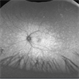

- Bilateral benign yellow dot maculopathy

- yellow dots, Autoflourescence

- A 37-year-old female patient presented for a routine eye examination. Her best-corrected visual acuity was 6/6 in both eyes. Fundus examination revealed multiple small yellow dots over the macula in both eyes. FAF imaging demonstrated characteristic hyperautofluorescence corresponding to these dots.